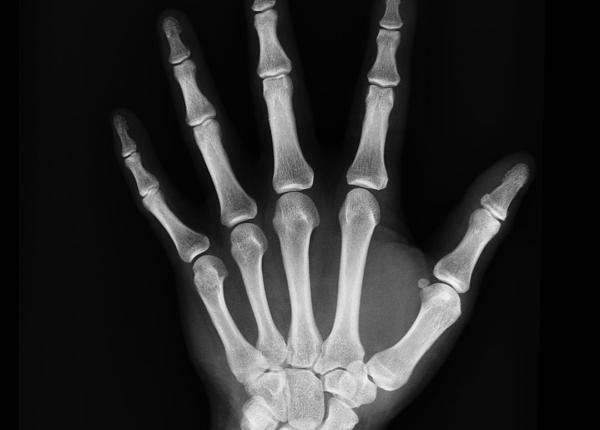

Factori care îți cresc riscul de fracturi osoase